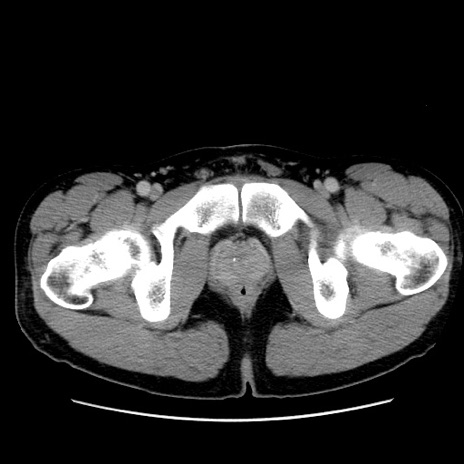

症例36(横断像)

【症例】20歳代 男性

【主訴】心窩部痛

【現病歴】今朝より上腹部痛あり。一旦軽快していたが再度出現したため救急要請。昨日夕に白身の魚を含む刺身を食べた。

【身体所見】BP 136/89mmHg、HR 74/min、BT 37.0℃、腹部:膨満、軟、心窩部に圧痛あり。反跳痛なし、筋性防御なし、腸雑音やや亢進あり。

【データ】WBC 17700、CRP 0.48